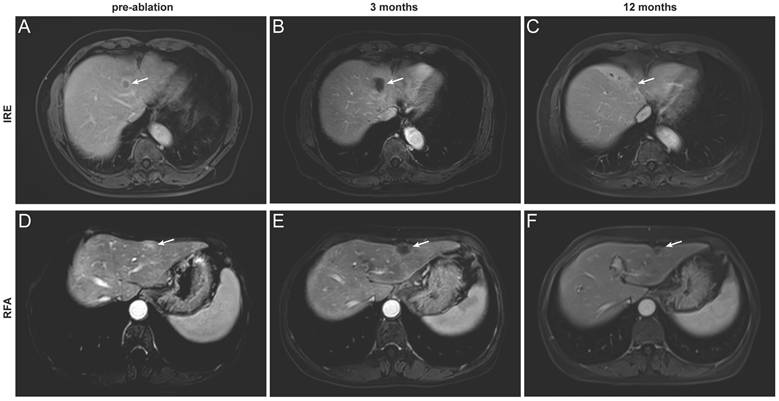

Based on the distinct ablation-zone remodeling patterns observed between IRE and RFA, clinical outcomes were further evaluated. LTP occurred in four patients after ablation, including three patients with secondary liver tumors and one patient with primary liver cancer (Table S1). The patient-level LTP rates were 18% in the IRE group and 15% in the RFA group (Table 3). For the primary endpoint, the median follow-up duration for LRFS was 40.5 months (range, 2-44.2 months). Kaplan-Meier analysis demonstrated no significant difference in LRFS between the IRE and RFA groups (Figure 4A). The LRFS rates at 6 months, 1, and 3 years were 90.9%, 81.8%, and 81.8% in the IRE group, respectively, and 100%, 91.7%, and 78.6% at the corresponding time points in the RFA group. Median LRFS was not reached in either group during the follow-up period. The overall ORR was 36.4% in the IRE group and 23.1% in the RFA group (Figure 4B). No significant differences were observed in PFS or OS between the two groups (Figure 4C, D). Representative cases are shown in Figure 5. Pre-ablation delayed-phase images depict the target lesions treated with IRE and RFA (Figure 5A and D). During follow-up, venous-phase images demonstrate well-demarcated hypoenhancing ablation zones at 3 months (Figure 5B and E) and 12 months (Figure 5C and F) after ablation, indicating complete lesion eradication.

Figure 5

Representative contrast-enhanced MRI images illustrating complete tumor ablation after IRE and RFA. (A-C) A 67-year-old man with hepatocellular carcinoma treated with IRE. Images obtained before ablation (A, delayed phase) and at 3 months (B) and 12 months (C) after ablation (portal venous phase); (D-F) A 64-year-old woman with colorectal liver metastasis treated with RFA. Images obtained before ablation (D, delayed phase) and at 3 months (E) and 12 months (F) after ablation (portal venous phase). The target lesion and ablation zone are indicated by arrows.